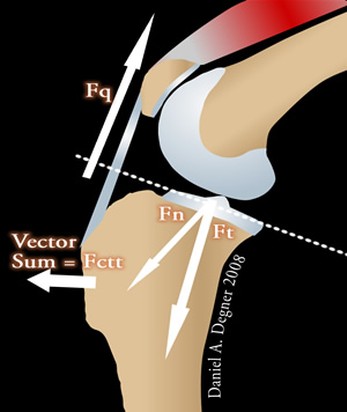

Secondo alcuni studi sulla biomeccanica dell’articolazione del ginocchio l’inclinazione del plateau tibiale rispetto all’asse della tibia stessa rappresenta un fattore determinante nella patogenesi delle rotture del legamento crociato craniale. Tale inclinazione è responsabile dell’intensità della “spinta tibiale craniale”, ossia di quella forza, generata dalla compressione tra femore e tibia durante il carico ponderale, che provoca la traslazione craniale della tibia, più l’inclinazione è elevata, maggiore sarebbe la spinta craniale della tibia.

- TTA è l'abbreviazione di tuberosità tibiale avanzamento.

E’ un intervento chirurgico intracapsulare per la terapia della rottura del legamento crociato craniale. La TTA fa parte delle tecniche chirurgiche che hanno come fine quello di ripristinare un equilibrio biomeccanico che neutralizzi la spinta craniale della tibia. L'obiettivo della chirurgia TTA è avanzare il sito di inserimento distale del tendine patellare cranialmente finché non è perpendicolare alla tangente comune che passa tra i condili femorali e quello tibiale. Gli impianti utilizzati per la TTA sono completamente in titanio. La chirurgia viene effettuata in Day-Hospital, nel post-operatorio è necessario osservare un periodo di convalescenza di circa un mese e mezzo.